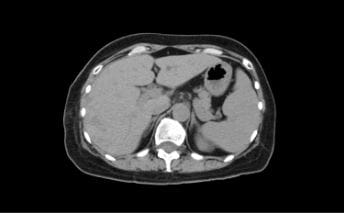

CT(コンピューターX線撮影)

CTはX線を使った人間の身体の透視画像を作ります。カメラが身体の周りをグルグル回り、輪切りの画像を何枚も撮り、単純な断層画像だけでなく、それらをつなぎ合わせて立体的な画像の作成もできます。

- 特長

- X線吸収差の大きい骨や肺の描出に優れている